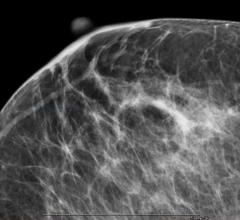

With all the conflicting information surrounding screening mammography, it is hard for breast radiologists not to be just as confused as the patients and referring clinicians. As a breast radiologist, I am passionate about breast imaging and the patients I serve.

Despite decades of progress in breast imaging, one challenge continues to test even the most skilled radiologists ...

In a study appearing in the April 26 issue of JAMA, researchers examined the content, readability and understandability of dense breast notifications sent to women following screening mammography.